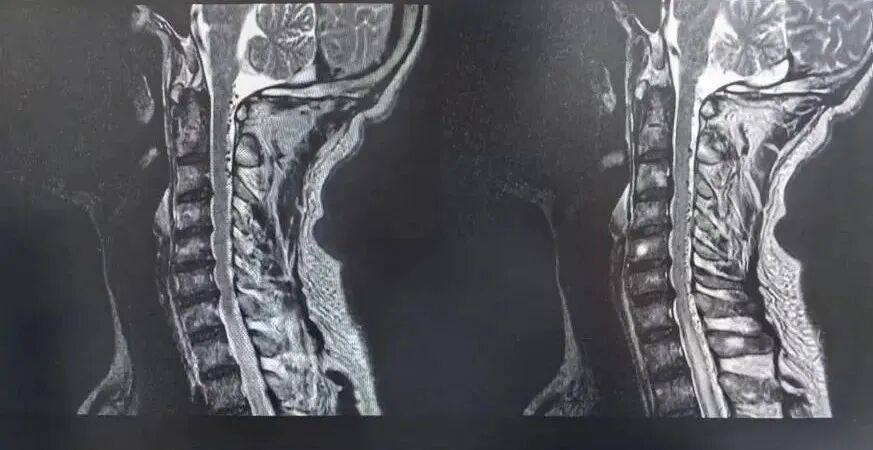

核磁共振檢查清晰可見脊髓背側(cè)“蚯蚓狀”血管

神經(jīng)外科團(tuán)隊?wèi){借扎實的神經(jīng)系統(tǒng)定位與定性的理論基礎(chǔ),結(jié)合患者癥狀,在核磁表現(xiàn)不典型的情況下不言放棄,鍥而不舍地查找病因。經(jīng)過集體討論,高度懷疑患者真正的病因是硬脊膜動靜脈瘺。

為進(jìn)一步明確診斷,神經(jīng)外科負(fù)責(zé)人景英朝主任帶領(lǐng)團(tuán)隊為患者進(jìn)行了脊髓血管造影,術(shù)中明確“頸5水平硬脊膜動靜脈瘺”!至此,幕后“元兇”終于浮出水面,病因精確鎖定為一種罕見疾病——硬脊膜動靜脈瘺。